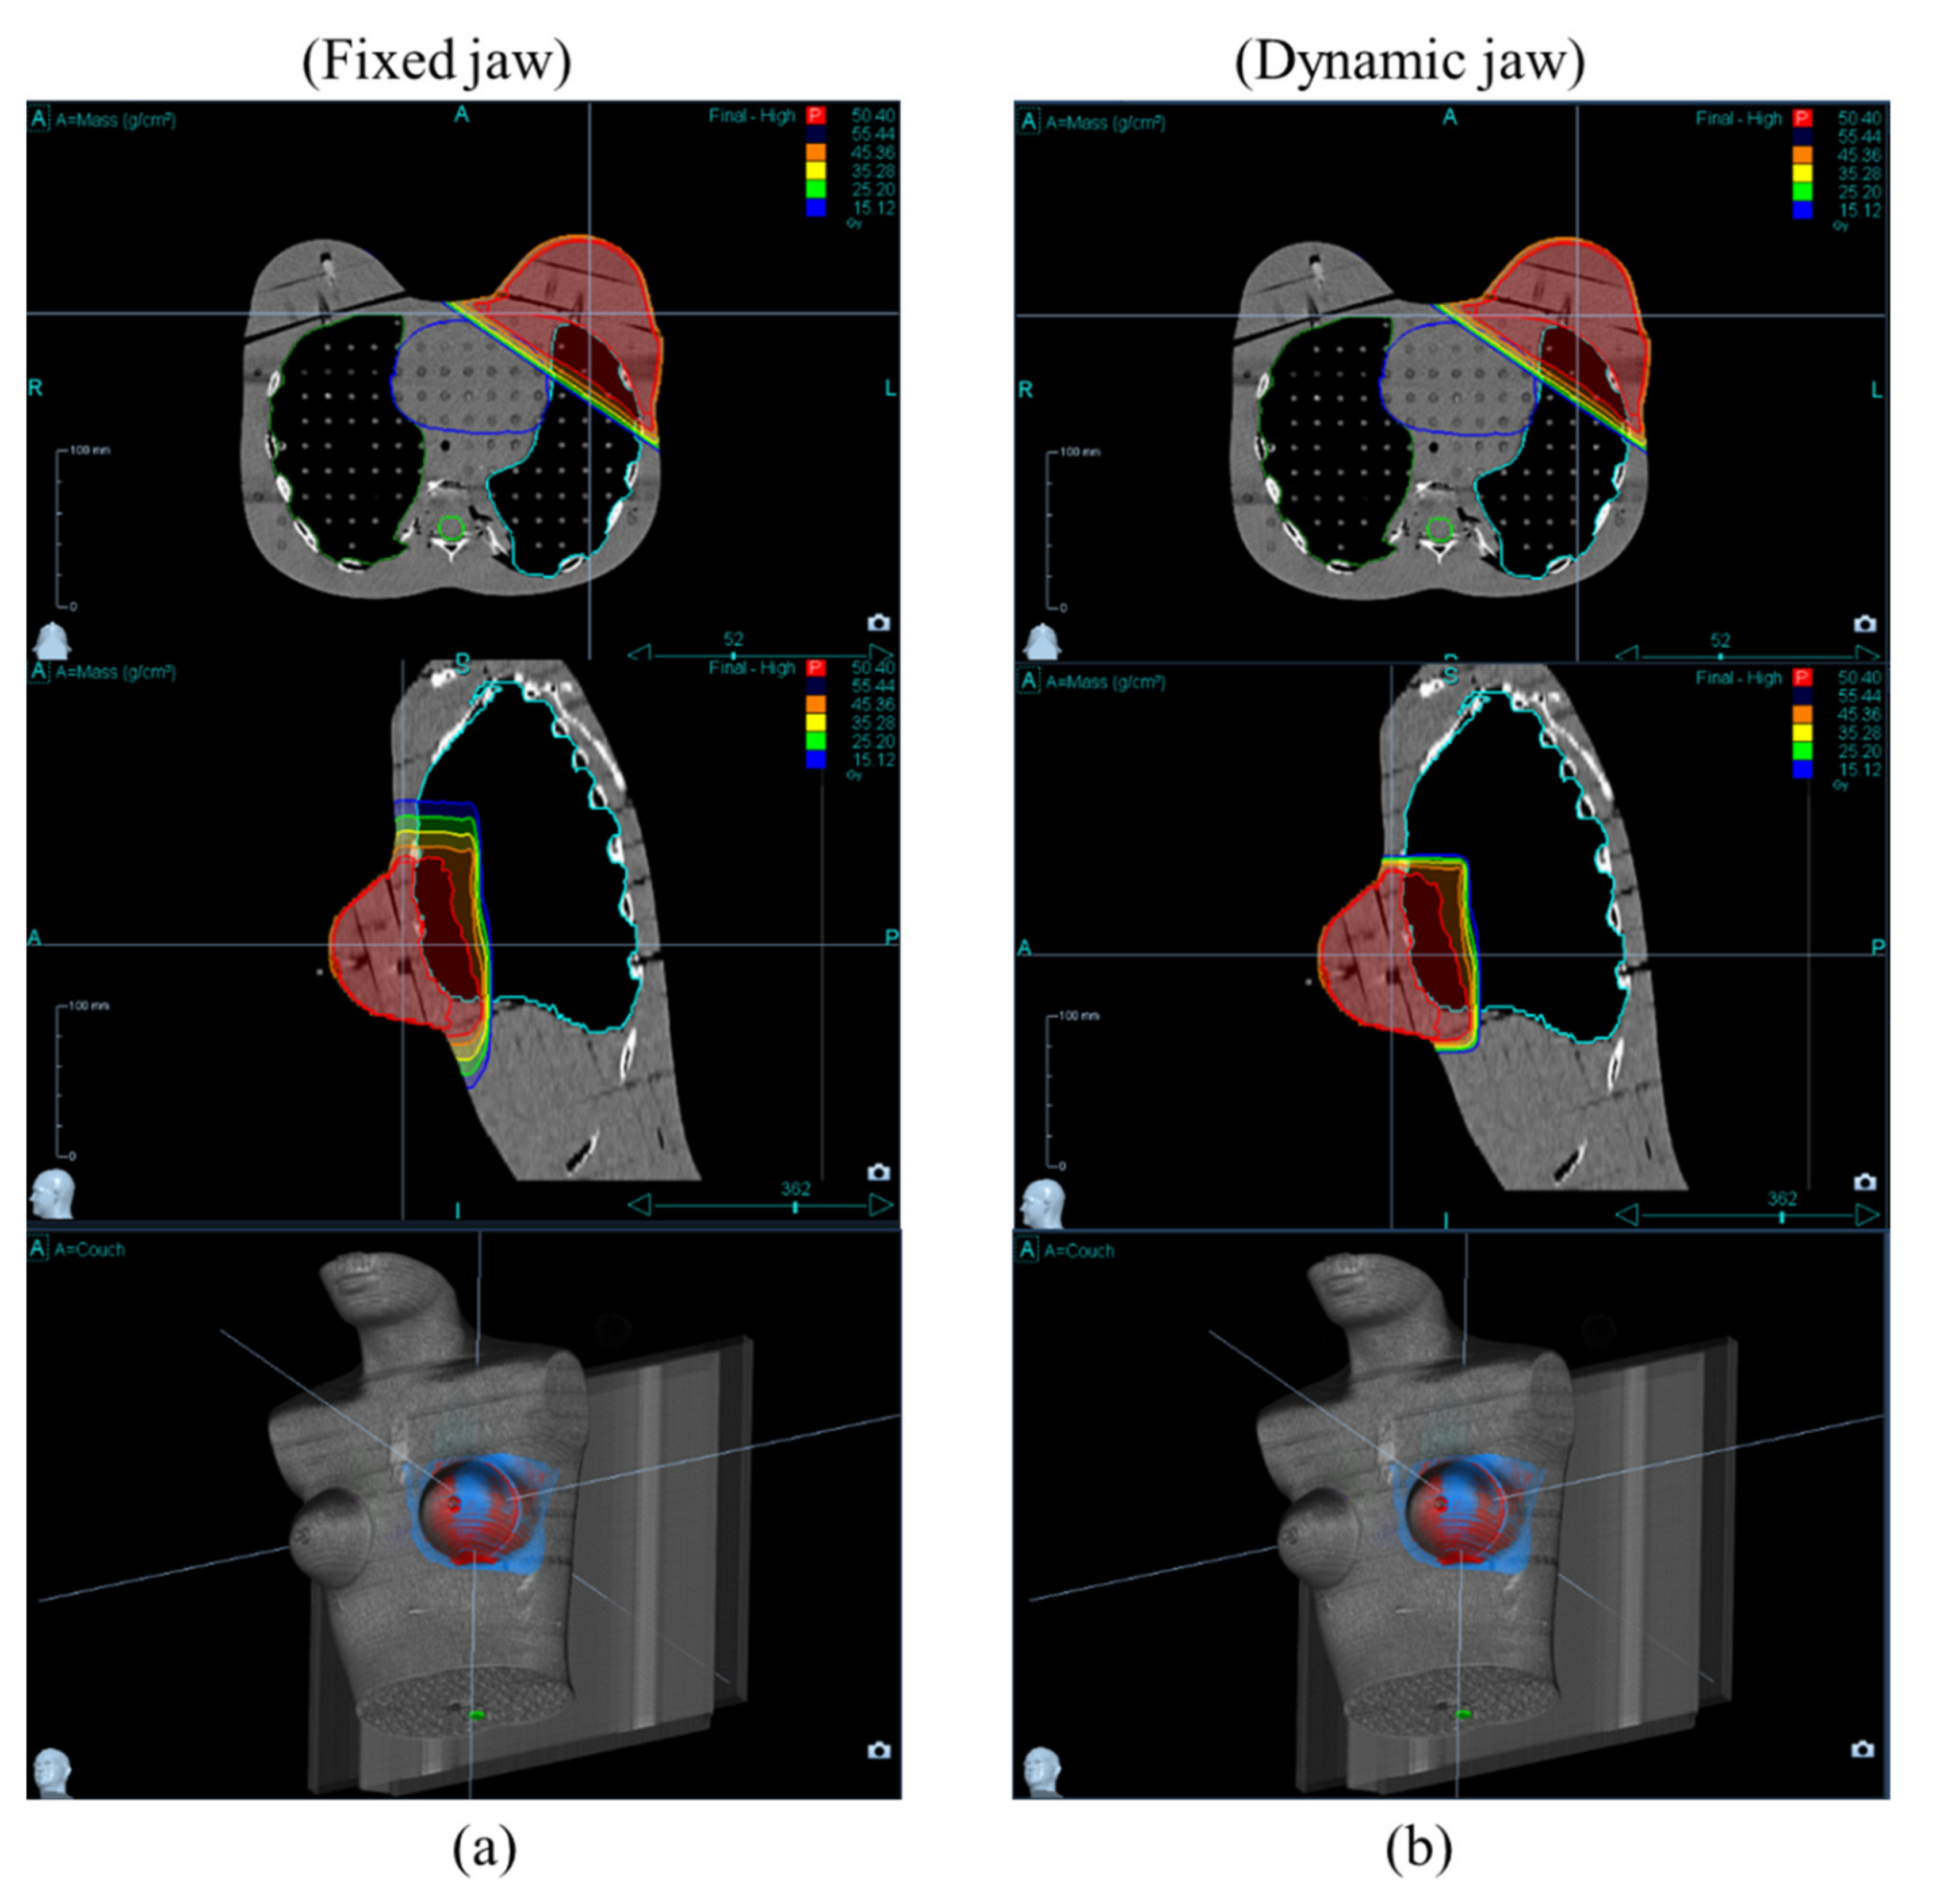

2.2. Treatment Planning

3. Results and Discussion

3.1. Target Coverage